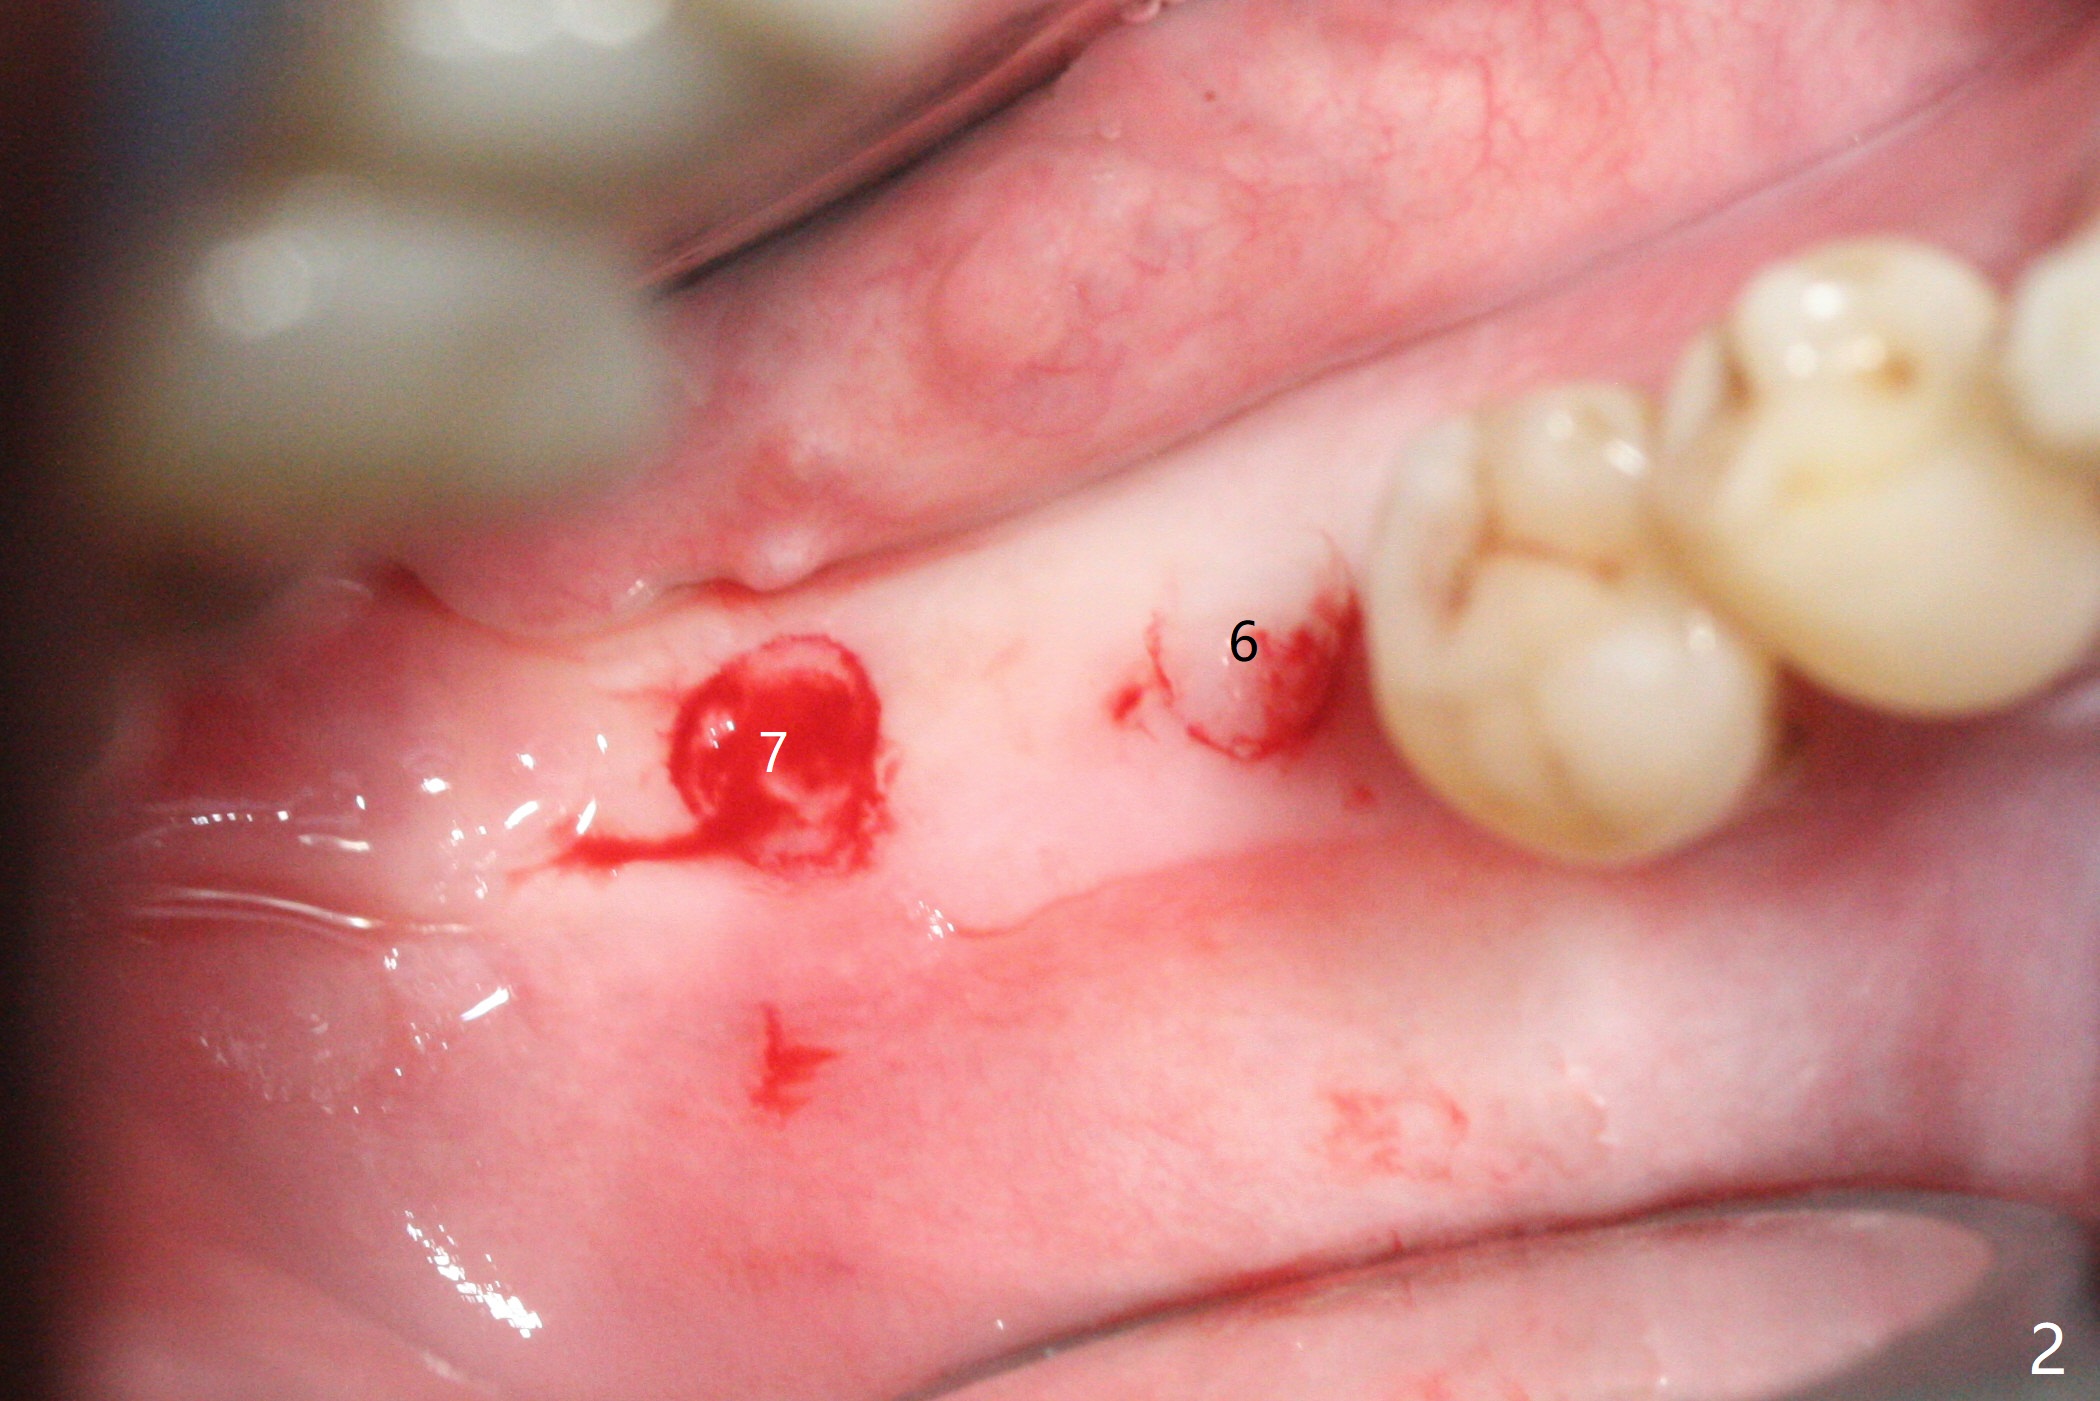

54岁男,右下6,7位点保留后7个月回来植牙,植牙床是个平面(图一),今后两个牙齿之间龈乳头一定缺乏,如何重建?放置导板,稍微使用环形钻头,在6,7植牙床上形成标记(图二),然后切开,植入植体,6扭力低,7高,所以安置愈合(6x5毫米)和修复(5.5x4(4)毫米)基台。原来导板设计把植体植入牙槽嵴(图三:白虚线)下1-2毫米,自动提高植体间牙槽嵴,接着把钻洞产生的骨粉放在后者上缘(*),由近中和远中基台固定。最后覆盖胶原膜,缝合(图四)。原来导板需要切除的角化龈保留住了(图四:7B,7L)。放入修复基台目的是利用它的高度固定牙周敷料。术后3个月7牙槽窝愈合(位点保存后10个月,图五:*),植体间牙槽嵴仍旧高(箭头),6放置修复基台,准备做临时牙冠。右上7反合,需要做局部矫正(图六)。病人非常感激术后三个月制作的临时牙冠(连体)。术后五个月对临时牙冠进行修改:6牙合面垫高(图七:*),这样上下7牙合面分开,上7颊侧放置矫正器,下7牙圈(舌侧有cleat),两者之间安置橡皮筋,上7就可以自由往舌侧移动。术后8.5个月全景片和CT显示植体种植牙槽嵴下(图八至十),这也是重建龈乳头基础。